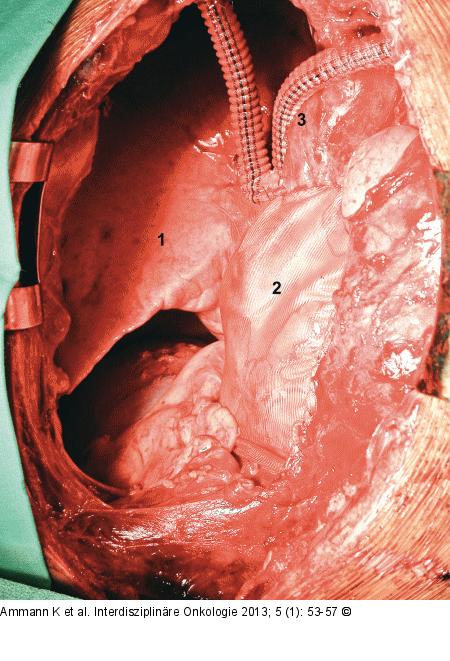

Abbildung 3: Thymus - Resektion Intraoperativer Situs nach Resektion des Thymus, obere Bilobektomie (1) (Lungenunterlappen) wegen pulmonaler Infiltration, Resektion des N. phrenicus, Perikardresektion und Resektion der Bifurkation der beiden Venae anonymae; Rekonstruktion des Perikards mittels Vicrylnetz (2), Gefäßrekonstruktion mittels YDacron- Prothese (3). Nach zusätzlicher adjuvanter Radiochemotherapie ist der Patient nach 5 Jahren immer noch rezidivfrei. |

Abbildung 3: Thymus - Resektion

Intraoperativer Situs nach Resektion des Thymus, obere Bilobektomie (1) (Lungenunterlappen) wegen pulmonaler Infiltration, Resektion des N. phrenicus, Perikardresektion und Resektion der Bifurkation der beiden Venae anonymae; Rekonstruktion des Perikards mittels Vicrylnetz (2), Gefäßrekonstruktion mittels YDacron- Prothese (3). Nach zusätzlicher adjuvanter Radiochemotherapie ist der Patient nach 5 Jahren immer noch rezidivfrei. |